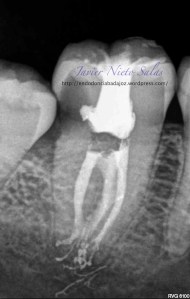

En el siguiente caso:

Se trata de una caso con una clasificación Tipo IIIb por el método de Min, ya pudimos sospechar que se trataba de un conducto en C:

Así podemos modificar nuestra técnica de obturación sabiendo que se trata de un sistema de conductos complicados

Con este par de casos quiero mostrar que  a todos nos sorprende, incluido yo,  la complejidad anatómica, pues nosotros SOLO conformamos, desinfectamos e intentamos obturar de la mejor manera, dejando la realidad del sistema de conductos en una interrogación a la que nos queremos acercar.